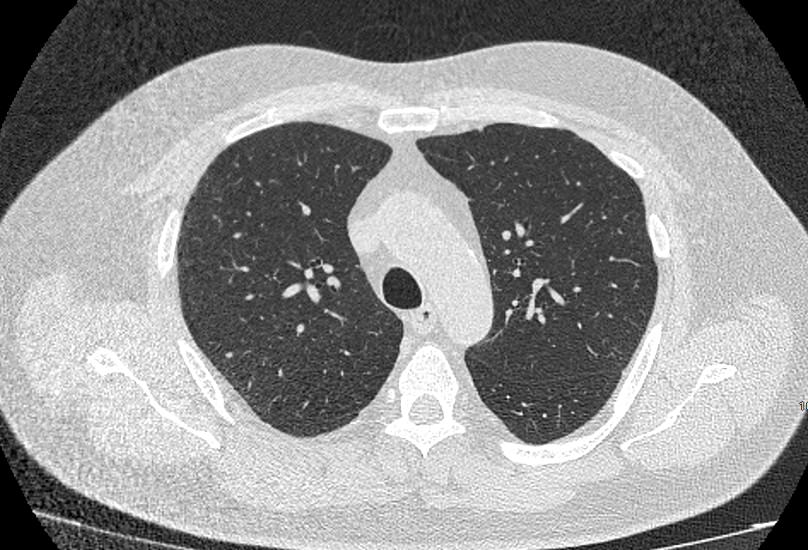

Во время исследования рентгеновская трубка томографа вращается вокруг исследуемой области и производит множество послойных снимков с шагом 0,5-1 мм. Полученные снимки поперечного сечения с помощью компьютерной программы могут быть преобразованы в 3D-изображения исследуемого органа или участка ткани. Это позволяет выявлять практически все заболевания легких на ранних стадиях и назначать своевременное лечение.

При проведении мультиспиральной КТ легких можно диагностировать различные заболевания, в том числе:

- Пневмонии (бактериальные и вирусные);

- Туберкулез легких;

- Рак легкого с определением стадии и распространенности процесса;